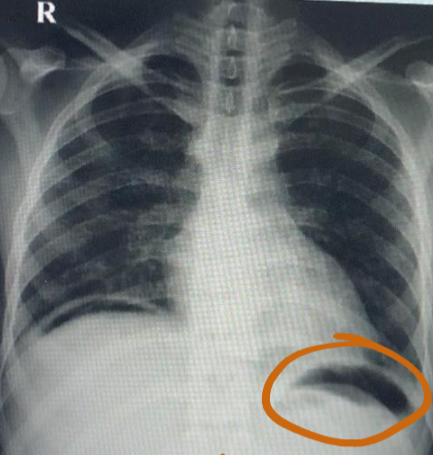

Q1: Name the (A) imaging study and (B) mention the main abnormality. (A) Erect chest X-ray. (B) Air under the diaphragm (pneumoperitoneum).

Q2: Name TWO clinical conditions where you can get this finding:

- Perforated bowel,

- post operative,

- injury as knife injury

Q3: Mention 4 important steps in the management including the most important if the patient is unstable clinically.

- FAST

- Keep NPO -NGT

- ABC

- Analgesia and antibiotics

- Surgery (most important if unstable)

Chest X-ray image obtained from a patient

Q1: What is your finding? Free air under diaphragm

Q2: Name TWO causes of this abnormality. Perforated duodenal ulcer, Penetrating trauma